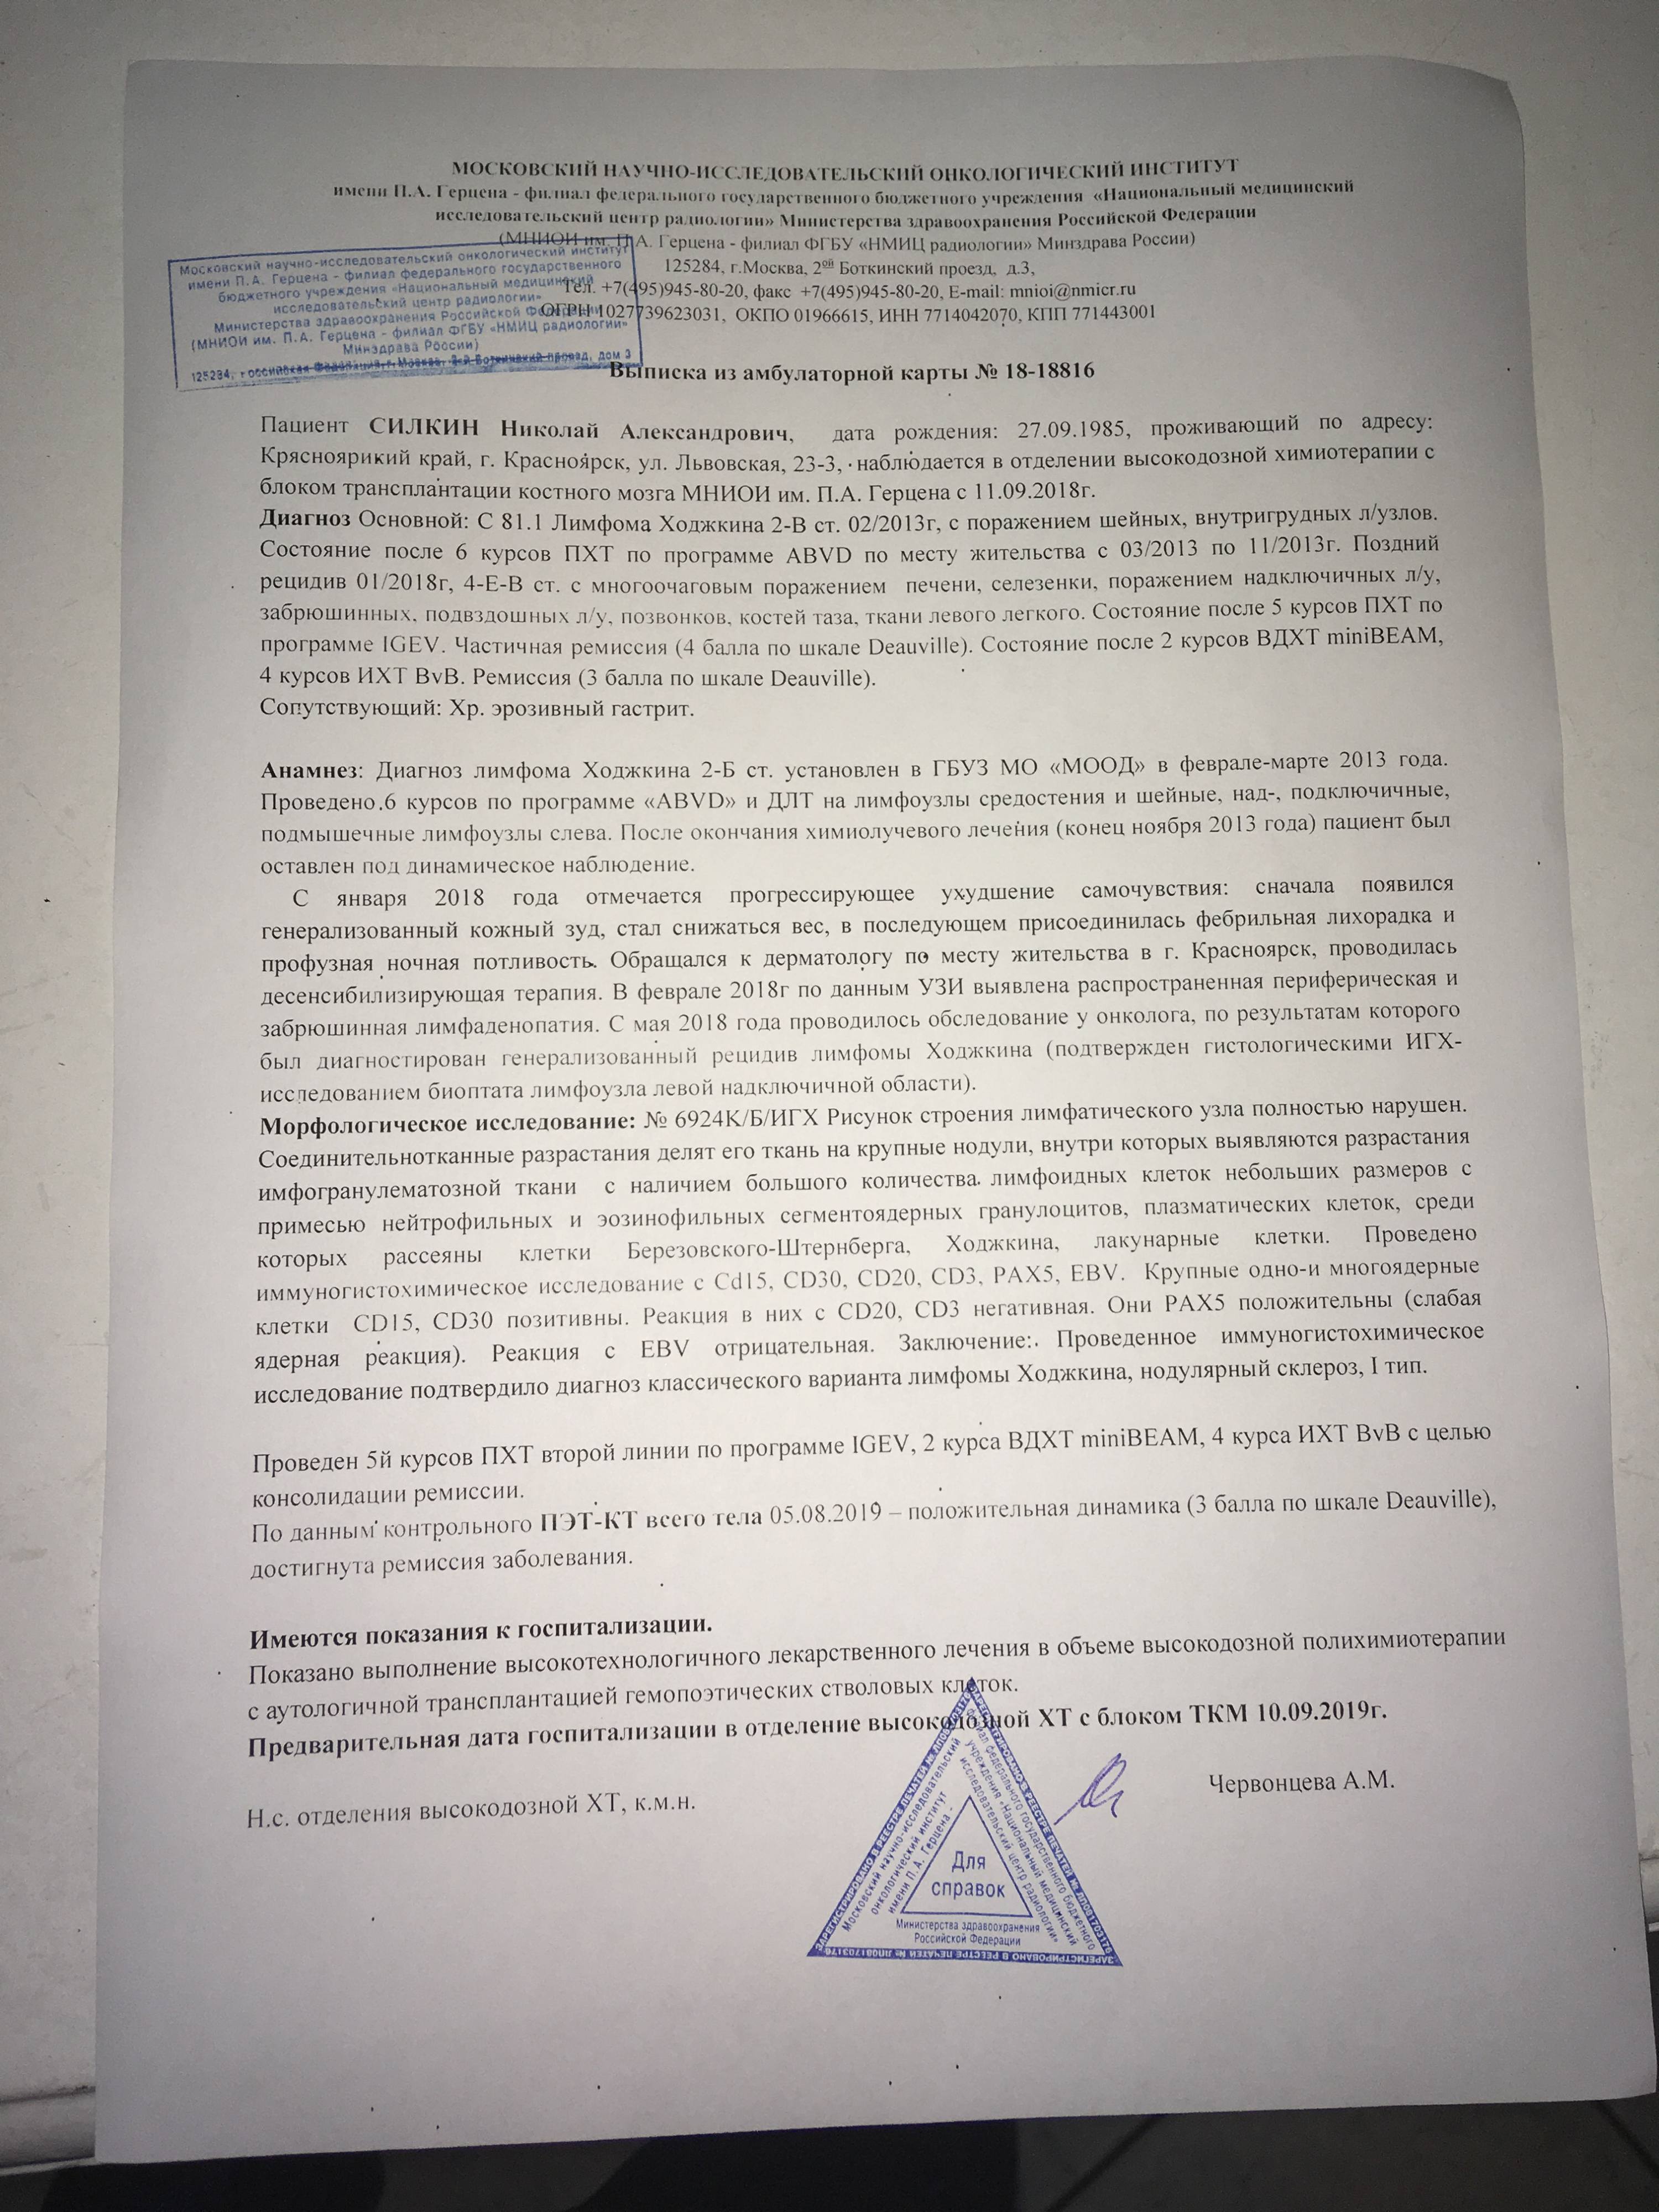

Диагностика лимфомы Ходжкина с помощью ПЭТ и КТ

Раздел: Светлые идеи